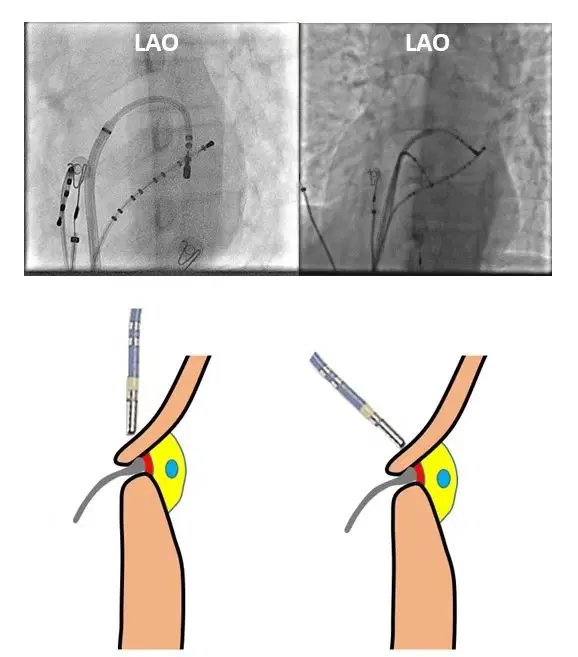

若为左侧游离壁旁道,可考虑更换8.5F SL1长鞘穿刺房间隔行二尖瓣房侧消融或重新穿刺右侧股动脉、使用抗折鞘逆行跨主动脉瓣行二尖瓣室侧消融。可以在心动过速下标测,也可以在心室起搏下标测理想靶点(小A中V,VA融合,A波最提前),35W✖55℃ 10秒内出现VA分离,然后沿着瓣环在靶点附近上下小幅度移动巩固消融60-90秒,然后使用ATP及静滴异丙肾上腺素、反复心内电生理检查未诱发心动过速,消融成功。

成功穿刺房间隔,送入消融导管过程中,一定要注意不能直顶!即导管进入左房后不能直着向前推送(心耳或左房顶部方向),否则容易出现心脏穿孔。消融导管进入左房中部后,将鞘管回撤,然后导管打弯、勾向二尖瓣环方向。